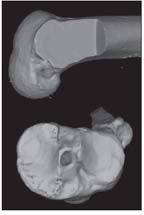

Knee injuries are the most common injury seen in skiing, and the incidence of anterior cruciate ligament (ACL) injuries is particularly high among competitive alpine skiers. A 3-dimensional CT scan shows a nonanatomical single-bundle AL reconstruction and demonstrates a posterolateral tibial tunnel and a “high” anteromedial femoral tunnel.